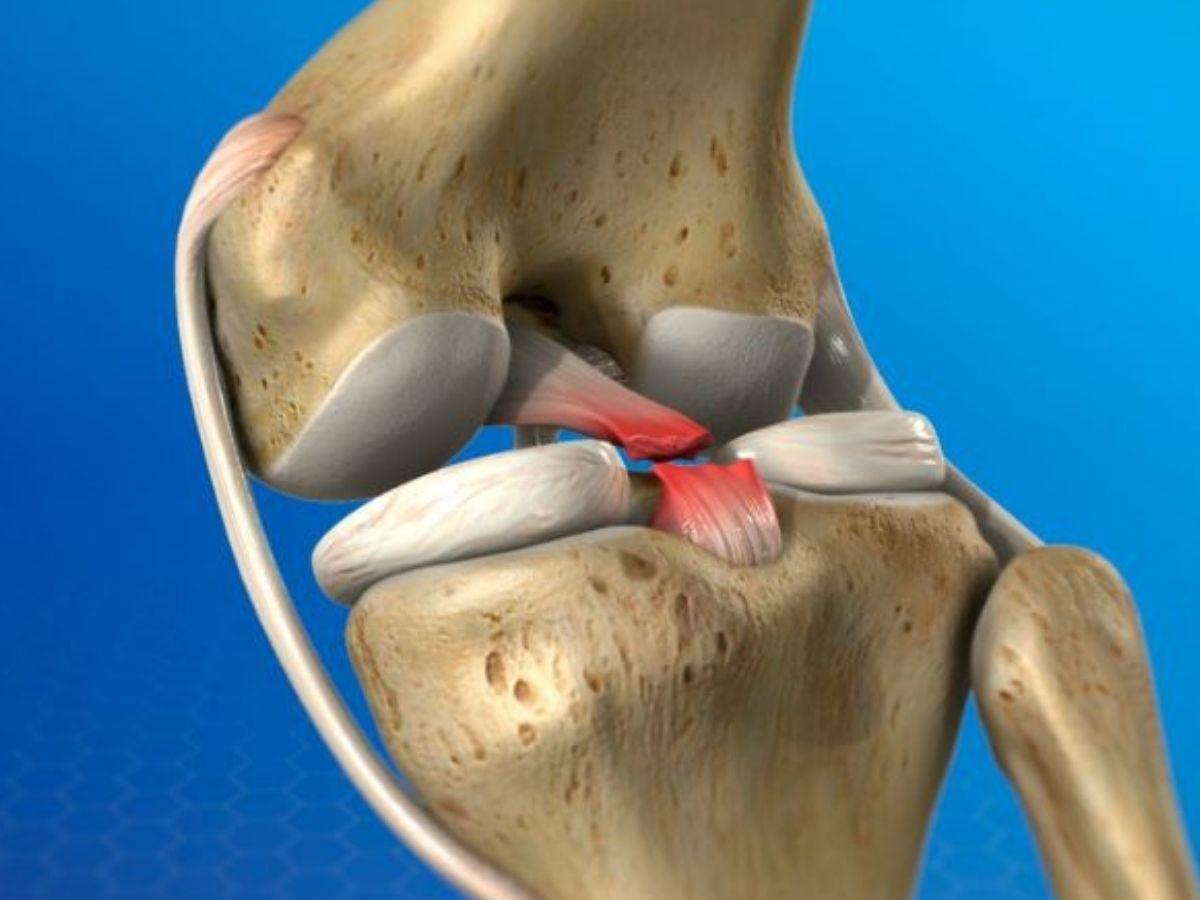

Cấu tạo khớp gối

Đầu gối là bộ phận kết nối hai phần xương ống chân và cẳng chân, kết cấu khớp có biên độ vận động lớn và có vai trò cực kỳ quan trọng trong quá trình di chuyển của cơ thể. Cấu tạo chính của khớp gối bao gồm:

Xương khớp gối: Bao gồm phần đầu dưới xương đùi, xương bánh chè và đầu trên xương chày. Trong số đó, phần xương bánh chè là bộ phận dễ bị tổn thương khi có tác động lực mạnh đến phần đầu gối, gây ảnh hưởng nghiêm trọng đến quá trình co duỗi và chuyển động của chân.

Gân cơ: Ở khu vực khớp gối có rất nhiều gân cơ với chức năng khác nhau như cơ tứ đầu, cơ bánh chè, gân cơ kheo và gân dải chậu chày.

Dây chằng: Khớp gối có bốn hệ dây chằng chính gồm dây chằng chéo trước, dây chằng chéo sau, dây chằng trong bên chày và dây chằng ngoài bên mác. Hệ thống dây chằng này giúp giữ vững hệ cơ khớp, liên kết và cố định cấu trúc chân. Đây cũng là bộ phận dễ bị tổn thương nhất khi vận động.

Sụn chêm khớp gối: Bao gồm sụn chêm trong và sụn chêm ngoài, nằm ở giữa hai đầu xương chày và xương đùi, có tác dụng phân tán và giảm lực tác động trong quá trình vận động.

Bao khớp: Đây là phần màng bao bọc bên ngoài khớp gối, có tác dụng tiết dịch bôi trơn để giúp hệ thống khớp hoạt động linh hoạt và dễ dàng hơn.

Cấu trúc cơ bản của khớp gối (Nguồn: Bệnh viện Đức Khang)